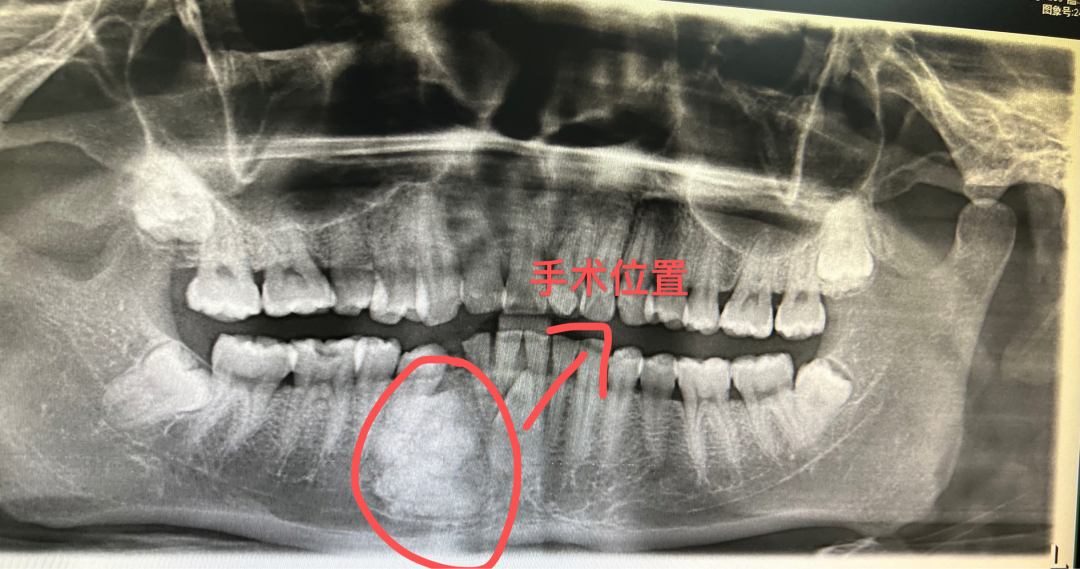

牙神經(jīng)活力測試:累及牙的牙神經(jīng)活力測試陽性。診斷爲牙骨質瘤。

▲術前口腔全景片

腫瘤多發(fā)生于磨牙或前磨牙的根尖部,與牙根融合;下颌比上颌多見,下颌第一磨牙區爲好(hǎo)發(fā)部位。腫瘤生長(cháng)緩慢,一般無自覺症狀,如腫瘤增大時(shí),可使牙槽骨膨脹,有時(shí)伴有神經(jīng)症狀。